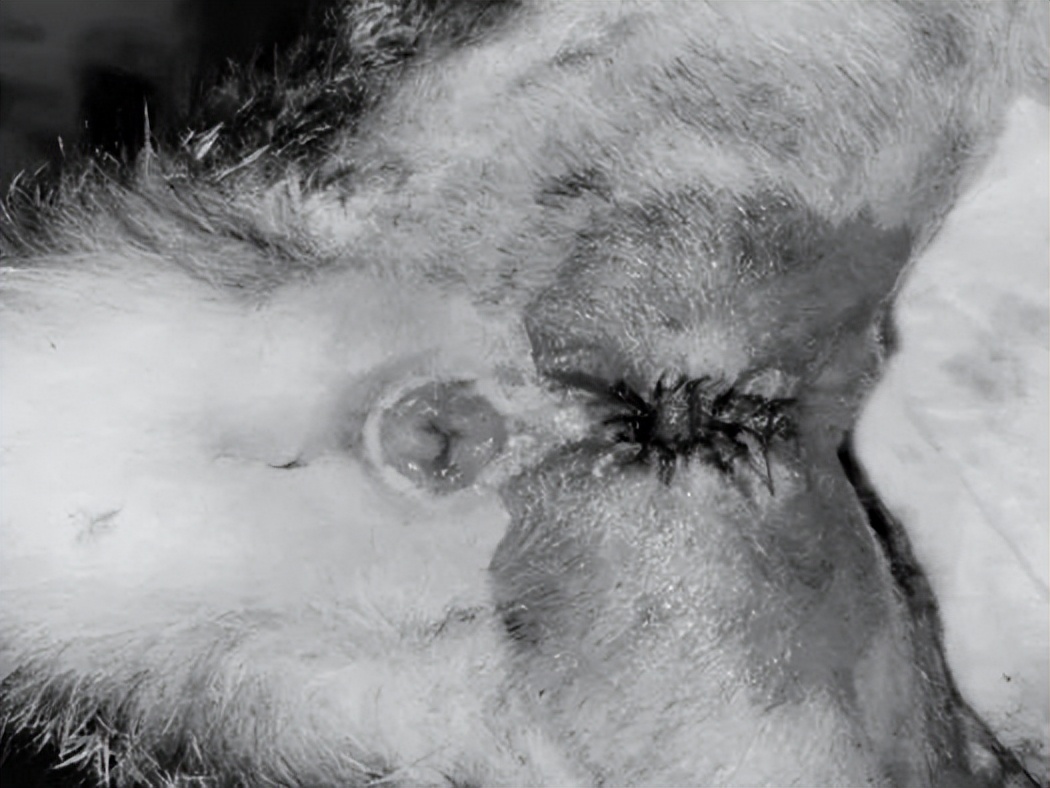

术后四周尿道口情况

但仍需停药后再做细菌培养定期复查

长期吃泌尿道处方粮,加大饮水量